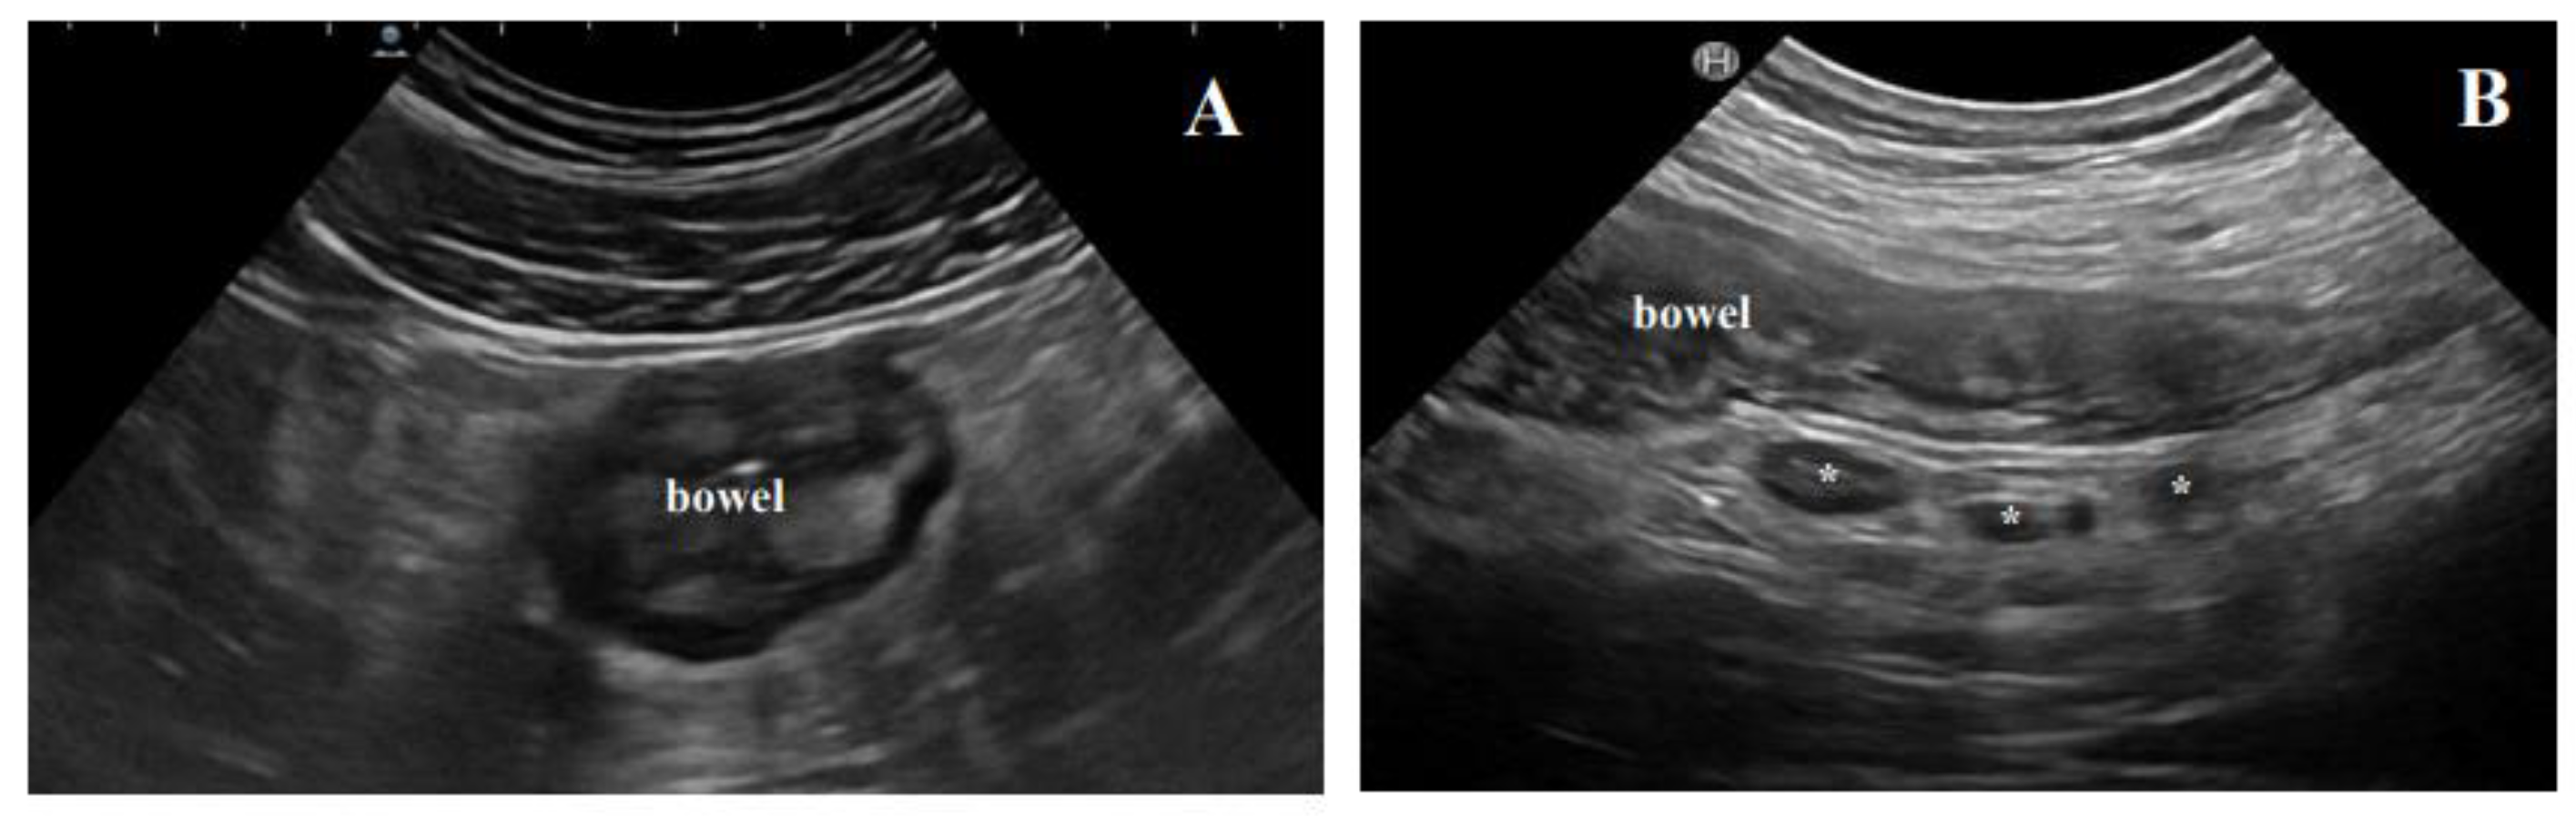

3.1. Ultrasound Features of CD